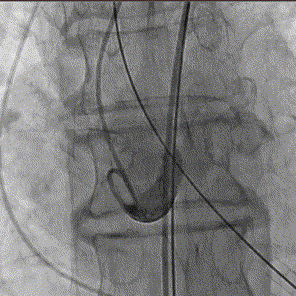

瓣膜释放过程

25mm球囊术前进行

瓣膜植入后25mm球囊进行后扩